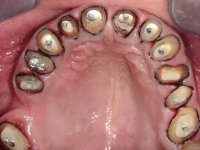

Paciente do sexo masculino, com 42 anos de idade, não fumador. Apresentava uma reabilitação metalo-cerâmica feita há mais de 10 anos com exposições radiculares e infiltrações. No maxilar superior apresentava uma coroa no 1.1,uma ponte de dois elementos no 2.1 e 2.2.e uma ponte de 4 elementos nos dentes 2.4,2.5,2.6 e 2.7 com o 2.6 como pôntico. Os dentes 1.6/1.5/1.4/1.3/1.2/1.1/2.1/2.2/2.3/2.4/2.5 e 2.7 apresentam tratamento endodôntico radical com o 2.4/2.5 e 2.7 a necessitarem de ser refeitos. No maxilar inferior apresentava uma ponte metalo-cerâmica de 4 elementos nos 4 incisivos e uma ponte de 3 elementos (3.3 e 3.4) com um dente supranumerário como pôntico. Os dentes 4.6/4.5 e 4.2 apresentavam tratamento endodôntico com o 4.2 a necessitar de ser refeito. Os dentes 4.3 e 4.4 apresentavam extensas cáries linguais com algum comprometimento mesial. As peças protéticas apresentavam-se infiltradas com exposição radicular associada. Apresentava uma D.V.O. diminuída e uma mordida cruzada lado direito. O paciente tinha uma satisfatória saúde periodontal e uma boa higiene oral.